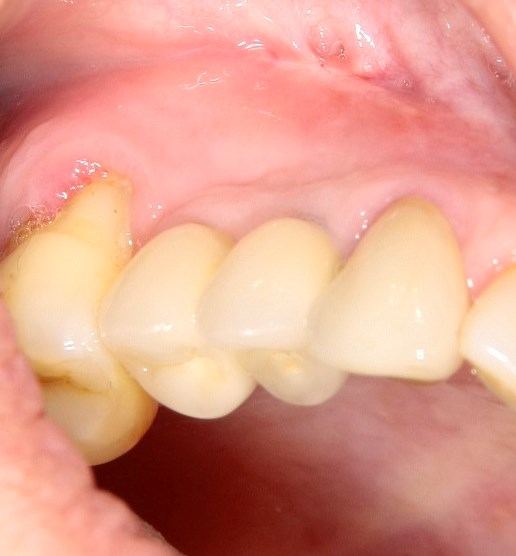

Опыт применения коллагеновой матрицы Mucograft в клинической практике.